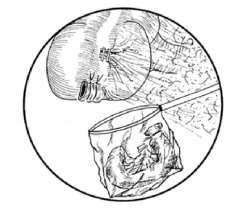

Posición de trócares y pinzas laparoscópicas correspondientes

Exploración e identificación del apéndice

Presentación y tracción del apéndice